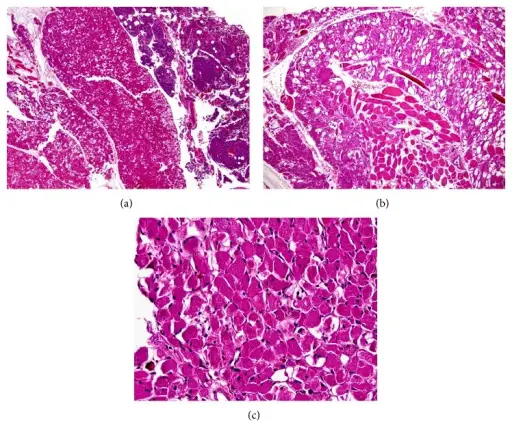

Rhabdomyomas are benign hamartomas of cardiac muscle.

Rhabdomyomas are the most common type of cardiac tumors in children.

Patients with tuberous sclerosis are at increased risk of rhabdomyomas.

Rhabdomyomas normally arises in the ventricle.